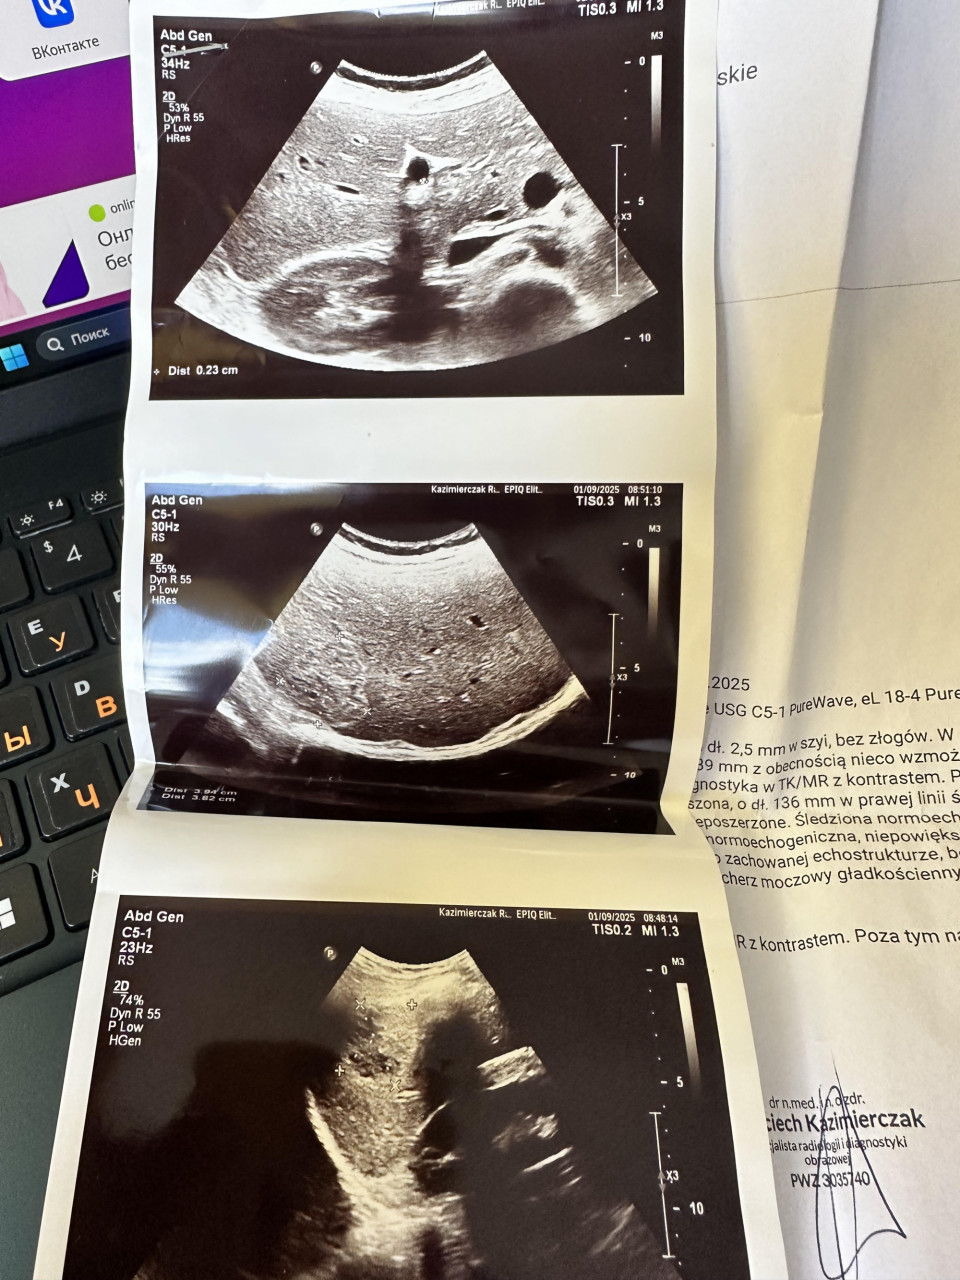

УЗИ

Печень была нормоэхогенной, не увеличенной, субкапсулярно в VI сегменте было видно четко очерченное, вероятнее всего инкапсулированное поражение со смешанной эхогенностью.

(частично изчастично гипоэхогенное), с сегментарно увеличенным кровотоком

по кругу 42 х 35 мм (без прогрессии в размерах по сравнению с предварительным обследованием от 01.09.2025 для дальнейшей диагностики на МРТ), без других четких очаговых

впечатлений.

Поджелудочная железа с типичной эхогенностью не увеличена.

Селезенка нормоэхогенная, не увеличенная.

Брюшная аорта не расширена.

Почки нормальной формы и размера, обе с сохраненной эхоструктурой, без признаков стаза

Поля надпочечников в доступных диапазонах свободны.

Мочевой пузырь без изменений.

Небольшое количество свободной жидкости внизу живота

В яичниках видны одиночные фолликулы, размером 30 х 20 мм в левом и 16 мм в правом, фолликул в правом яичнике с сегментарно утолщенной стенкой до 4,5 мм, вероятно, осложненный кровотечением - необходим гинекологический осмотр в следующем цикле.